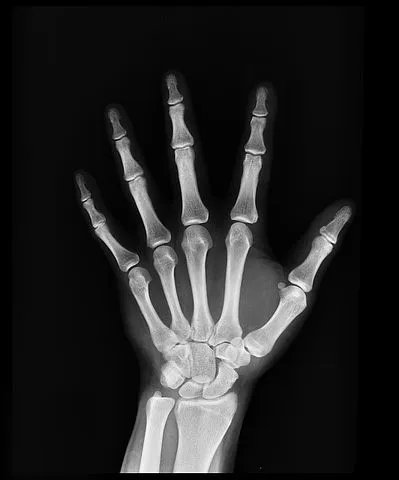

내 손가락 뼈 사진을 들여다보던 의사는 무덤덤했다. 별 진단 없이 진료를 끝내려는 의사에게 황급히 말했다.